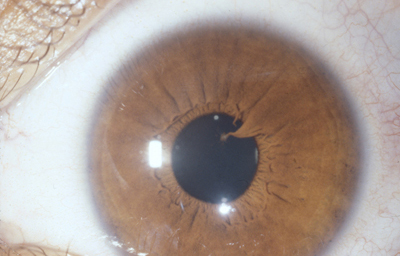

Colobomas típicos con diferentes grados de defecto en el desarrollo

Colobomas Atípicos.

Archivo Fotográfico Dr. Francisco Barraquer

Archivo Fotográfico Dr. Francisco Barraquer